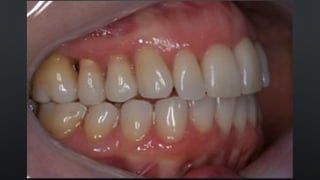

• OCLUSÃO HABITUAL, DETERMINADA PELOS DENTES

RELAÇÃO ENTRE ARCOS

MÁXIMA INTERCUSPIDAÇÃO HABITUAL (MIH)

• OCLUSÃO ONDE SE OBTÉM O MAIOR NÚMERO DE CONTATOS DENTAIS

POSSÍVEIS

• POSIÇÃO DE REABILITAÇÃO EM PACIENTES DENTADOS COM OCLUSÃO

ESTÁVEL

• OCLUSÃO HABITUAL,DETERMINADA PELOS DENTES RELAÇÃO ENTRE ARCOS MÁXIMA INTERCUSPIDAÇÃO HABITUAL (MIH) • OCLUSÃO ONDE SE OBTÉM O MAIOR NÚMERO DE CONTATOS DENTAIS POSSÍVEIS • POSIÇÃO DE REABILITAÇÃO EM PACIENTES DENTADOS COM OCLUSÃO ESTÁVEL